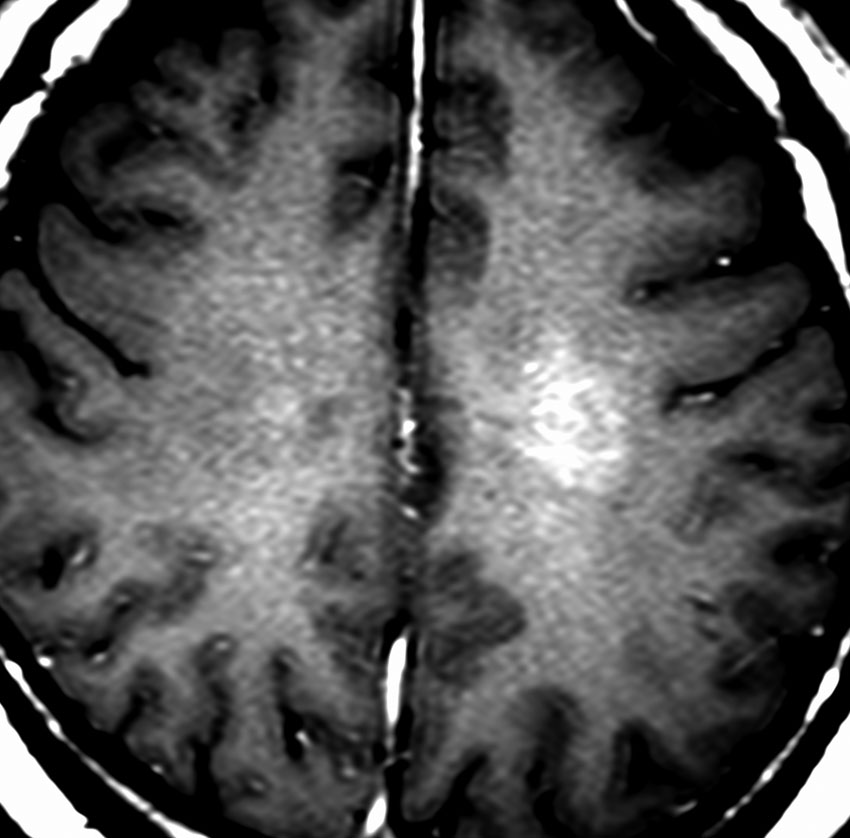

40代の患者さんです。夜間睡眠中の全般発作(症候性てんかん)で発症しました。フレア画像で左上前頭回に滲むような高信号領域(白い部分)がみられます。右側はガドリニウム増強MRIですが,全く増強されません。グレード2か3の星細胞腫あるいは乏突起膠腫を疑います。白く滲むような領域はよく見るとかなり広範囲に広がっています。

画像上では全摘出 gross total removalできて,病理診断は,退形成性乏突起星細胞腫 anaplastic oligoastrocytomaでした。IDH変異あり,1p/19q欠失なしです。現在の診断なら,退形成性星細胞腫 グレード3です。